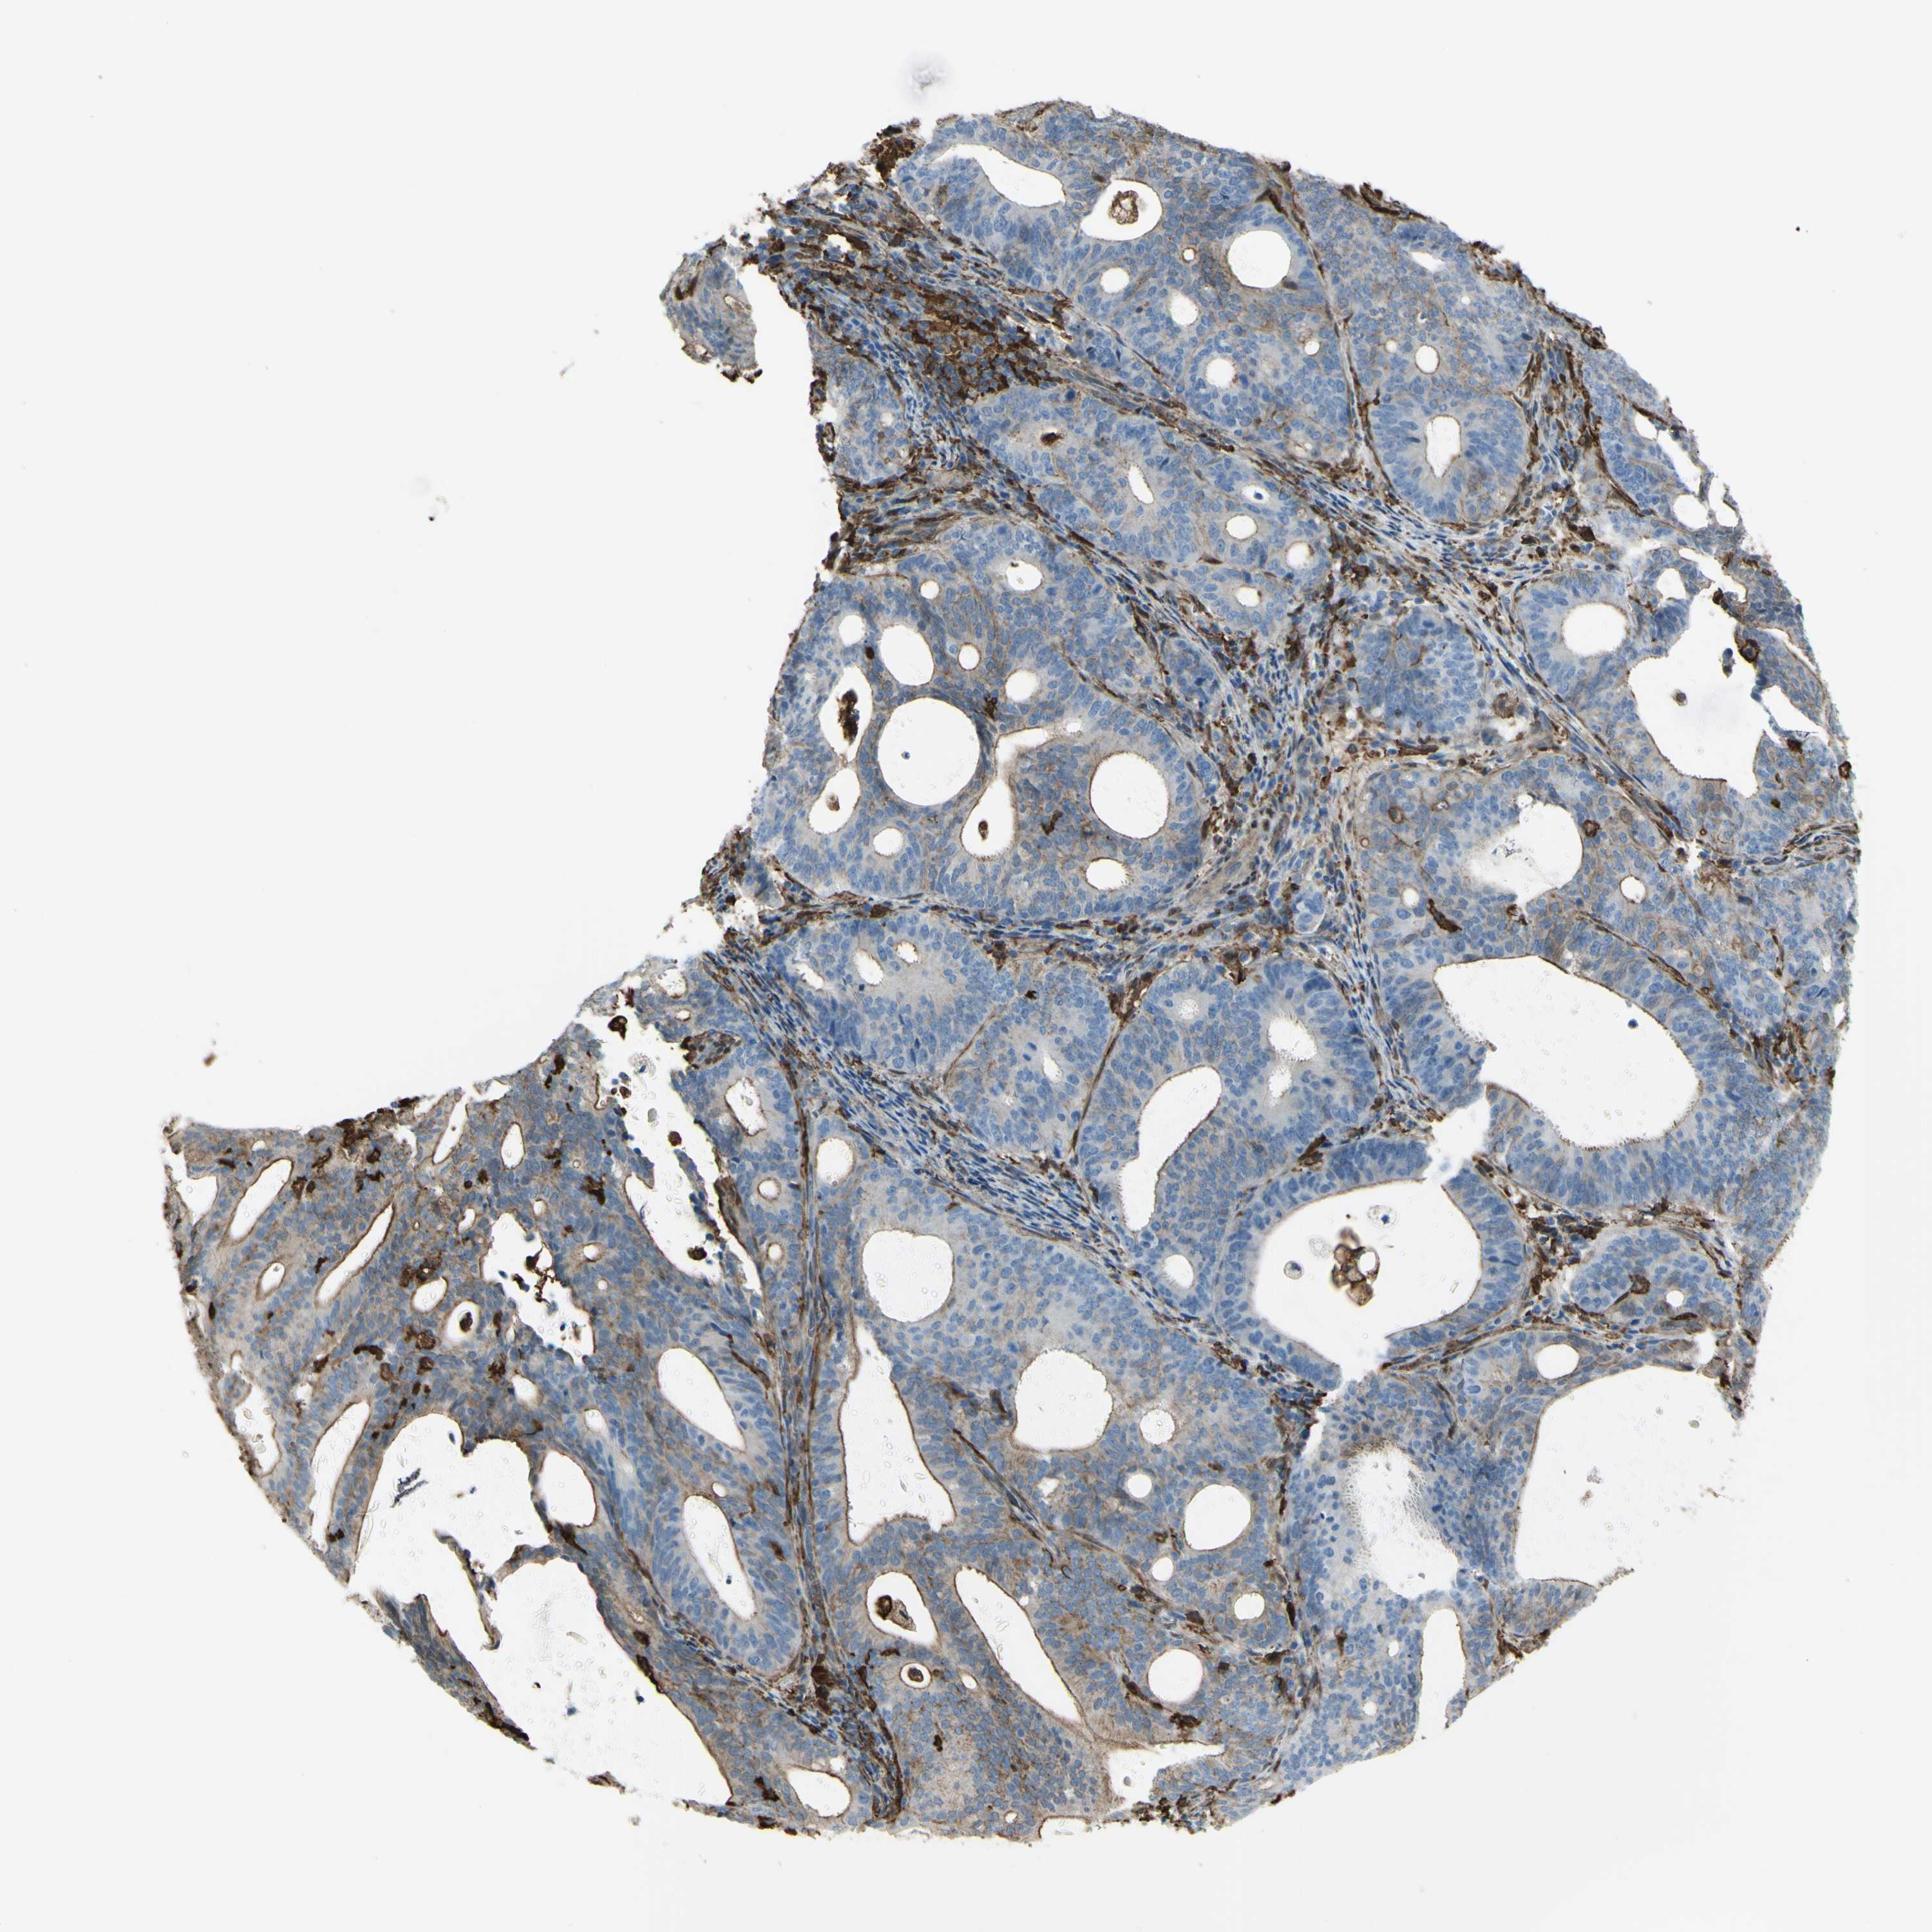

ENDOMETRIAL CANCER - Protein expressioni

A mouse-over function shows sample information and annotation data. Click on an image to view it in a full screen mode. Samples can be filtered based on level of antibody staining by selecting one or several of the following categories: high, medium, low and not detected. The assay and annotation is described here.

Note that samples used for immunohistochemistry by the Human Protein Atlas do not correspond to samples in the TCGA dataset.

Antibody stainingi

Antibody staining in the annotated cell types in the current human tissue is reported as not detected, low, medium, or high, based on conventional immunohistochemistry profiling in selected tissues. This score is based on the combination of the staining intensity and fraction of stained cells.

Each image is clickable and will lead to virtual microscopy that enables deeper exploration of all samples and also displays staining intensity scores, fraction scores and subcellular localization as well as patient and tissue information for each sample.

Antibody HPA054026

Antibody CAB010823

Antibody CAB016728

Antibody CAB036009

Staining

High

Medium

Low

Not detected

Intensity

Strong

Moderate

Weak

Negative

Quantity

>75%

75%-25%

<25%

None

Location

Nuclear

Cytoplasmic/membranous

Cytoplasmic/membranous,nuclear

Adenocarcinoma, NOS

Adenocarcinoma, metastatic, NOS